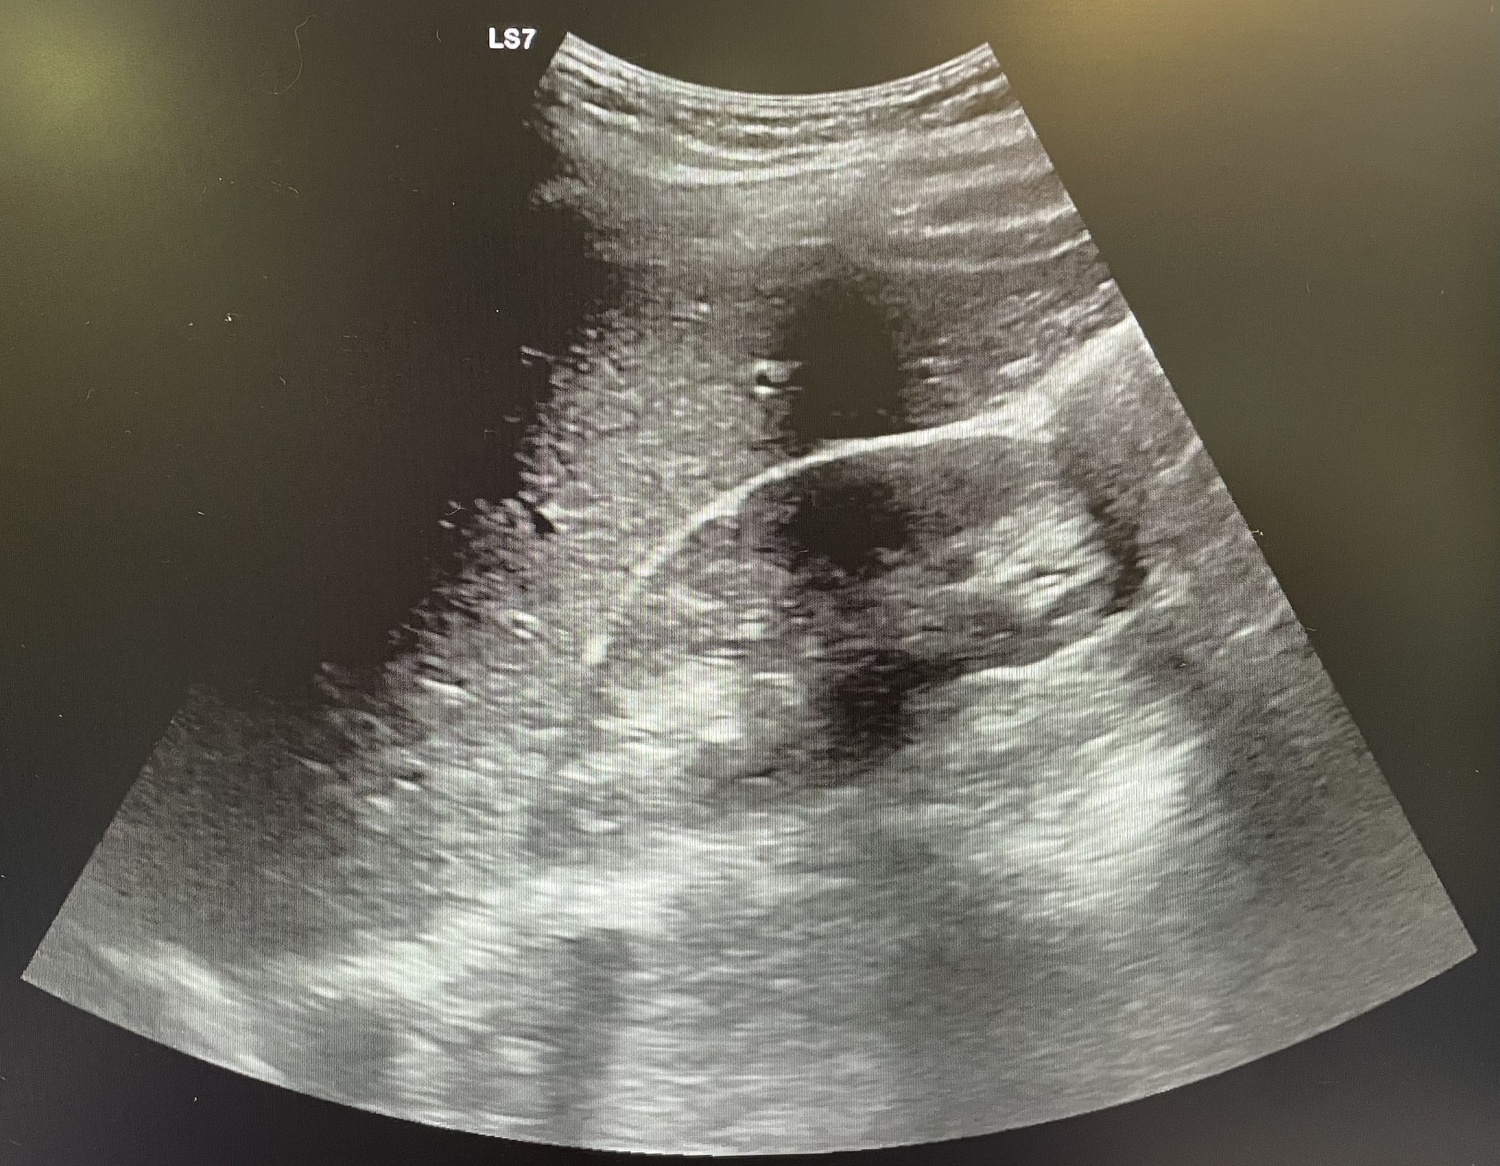

Se realiza analítica con aumento de reactantes de fase aguda (leucocitos 18.00 y PCR 108) y se indica ecografía abdominal que resulta no concluyente, por lo que se procede a alta.

Al día siguiente vuelve con la misma sintomatología, el dolor no cede con analgesia habitual. En la exploración Blumberg claramente positivo, se solicita analítica (leucocitos 13.000 y PCR 127) y se repite ecografía de abdomen que se sigue informando como no concluyente para apendicitis aguda.

La paciente vuelve a acudir a urgencias con la misma sintomatología por lo que decide realizar TAC donde se observa apendicitis evolucionada, se contacta con cirugía que ingresa al paciente por plastrón apendicular.